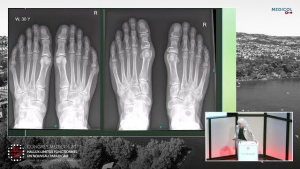

Hallux Rigidus

Dre Barbara Piclet - Congrès Medicol 2023

2023

congrès medicol

pied

piclet